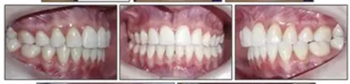

6年后治療結(jié)果保持穩(wěn)定(圖11,圖12 ; 圖13)??梢杂^察到穩(wěn)定的間隙關(guān)閉,正常的覆蓋和覆合,上下牙中線一致,微笑美觀。建議完美替代了拔除的側(cè)切牙。正畸治療后進行牙齒美白。